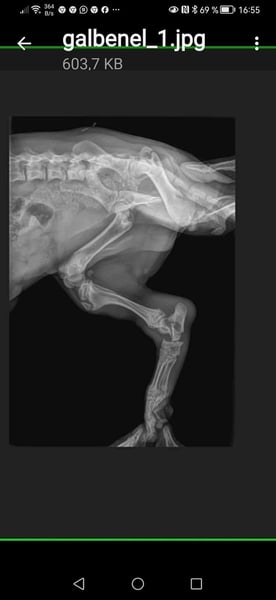

▪️ ausgesetzt auf der Straße mit einem gebrochenen Bein und einer riesengroßen Hernie...

Mit einer Hernie... Eine Luxation und ein Bruch am Bein

wurde er von einer Tierschützerin auf der Straße aufgegriffen..

▪️Hernie operiert und Kastration durchgeführt...

▪️ Als die erste OP verheilt war, wurde PomPom nach vorheriger Absprache noch noch einige weitere Male unserem Tierarzt vorgestellt..

▪️Um zu schauen ob man an seinem Beinchen noch operieren muss.....

Oder ob man es so lässt...

weil man auch manchmal durch eine OP nichts verbessern,

sondern eher schlimmer machen kann.

⏯️Weil oft auch weniger mehr ist⏮️

Es wurde dann festgestellt der Bruch wächst sehr gut zusammen und der kleine Mann, wird vermutlich keine Einschränkungen mehr haben.

▪️ Wir haben damals gemeinsam mit unserem Tierarzt vereinbart, den kleinen Mann über einen längeren Zeitraum alle paar Monate regelmäßig vorzustellen, ob sich noch irgendetwas nachteilig verändern würde.

▪️ PomPom wurde von unserem Tierarzt, nach der ersten großen OP in regelmäßigen Abständen wieder vorgestellt und der Bruch wurde immer wieder kontrolliert.

▪️ Und die Meinung unseres tollen Tierarztes war wie immer richtig.

▪️Der komplizierte Bruch verheilte perfekt ohne weitere OP problemlos.

▪️ PomPom läuft heute ohne weitere gesundheitliche Einschränkungen.